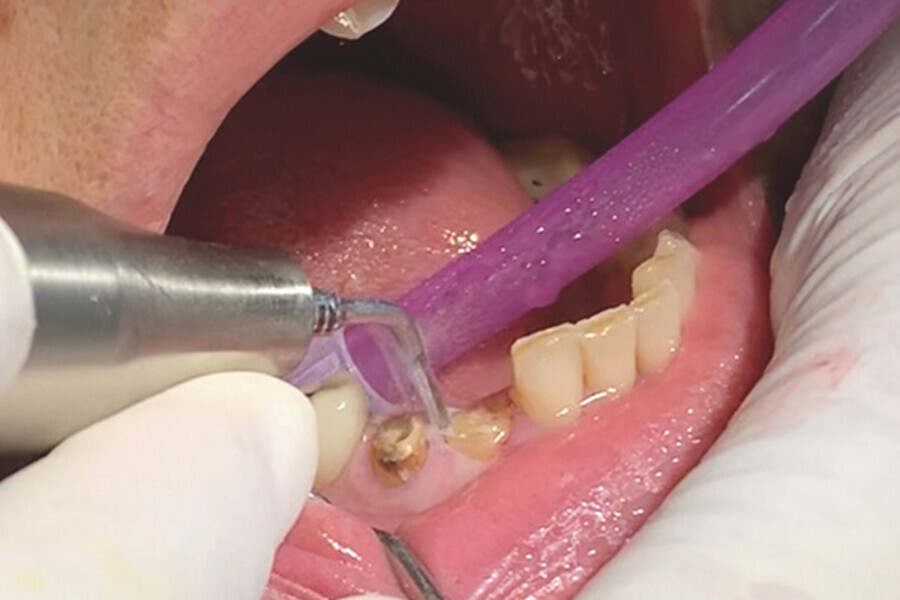

Figs. 7. Remoción delicada de los restos radiculares y comproba

Figs. 8. Remoción delicada de los restos radiculares y comproba